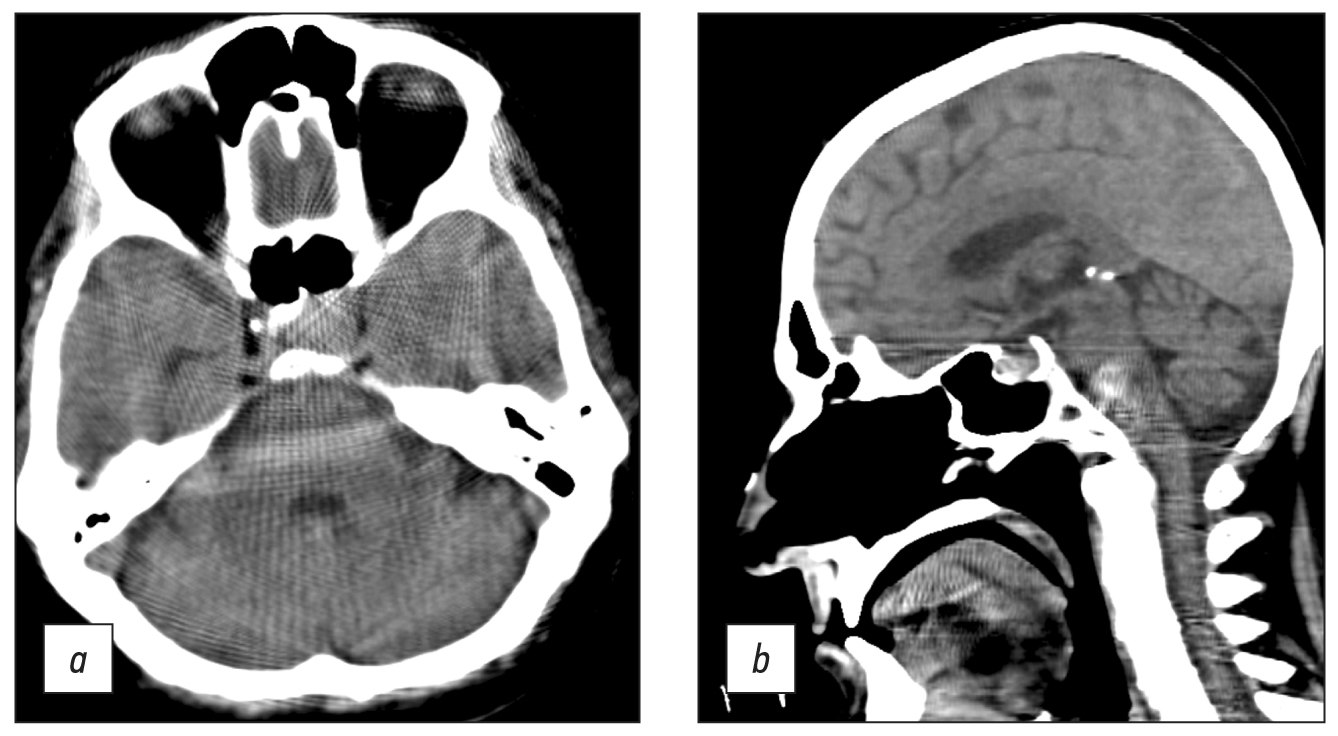

Windmill artifacts (Fig. 8a) were mixed with strike artifacts and helical scanning [5], and artifacts intensified at the level of skull base, where significant beam hardening and scattering artifacts occurred (Fig. 8, b). Therefore, subtentorial brain areas were challenging to assess.

Fig. 8. Axial (a) and sagittal (b) computed tomographic images of the head in the region of the posterior cranial fossa and base of skull showed windmill, strike, beam hardening, and scattering artifacts. Area of bone structures and the posterior fossa is hard to evaluate.